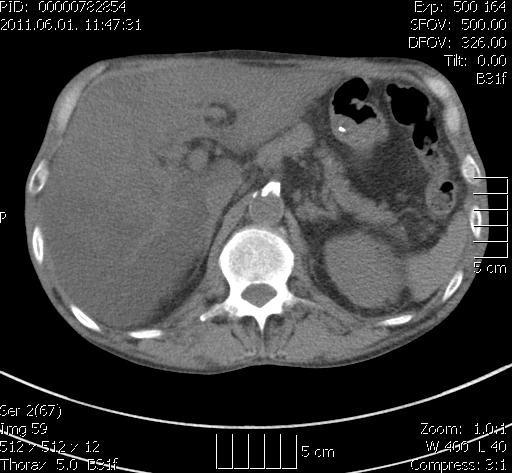

| mellkas Ct vizsgálat (hasi szelet) axialis rekon – a lig falciforme hepatis mellett egynemű, sűrű folyadék densitású képlet |